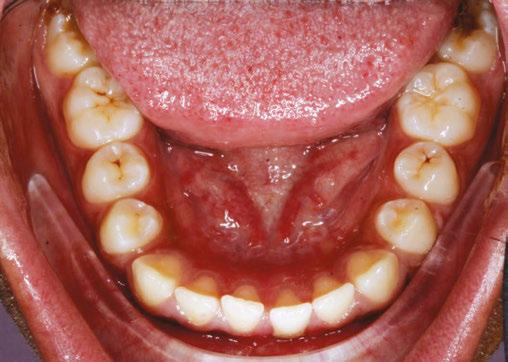

Figure 2: Initial lower occlusal

Figure 1: Initial center photo

This case involves a 13-year-old female patient with a complex malocclusion that includes multiple dental and skeletal issues. During the initial consultation, clinical evaluation showed severe maxillary crowding along with generalized spacing in the mandibular arch. The patient’s occlusal relationships were asymmetric, with a Class I molar relationship on the right side and a Class II molar relationship on the left. Notably, an anterior crossbite was observed, further complicated by a narrow, V-shaped maxillary arch — a common presentation that often exacerbates anterior-posterior discrepancies and limits functional occlusion. The patient also demonstrated poor oral hygiene, which is a key indicator of an indirect bonding system that does not reduce excess flash. ODB is superior in flash reduction, by being able to remove excess adhesive from three sides of the bracket instead of competitors who only remove adhesive from one side of the bracket. The presence of adhesive around brackets contributes to surface roughness which leads to plaque accumulation.1 Flash reduction will be very important for every patient’s orthodontic success (Figures 1-3).